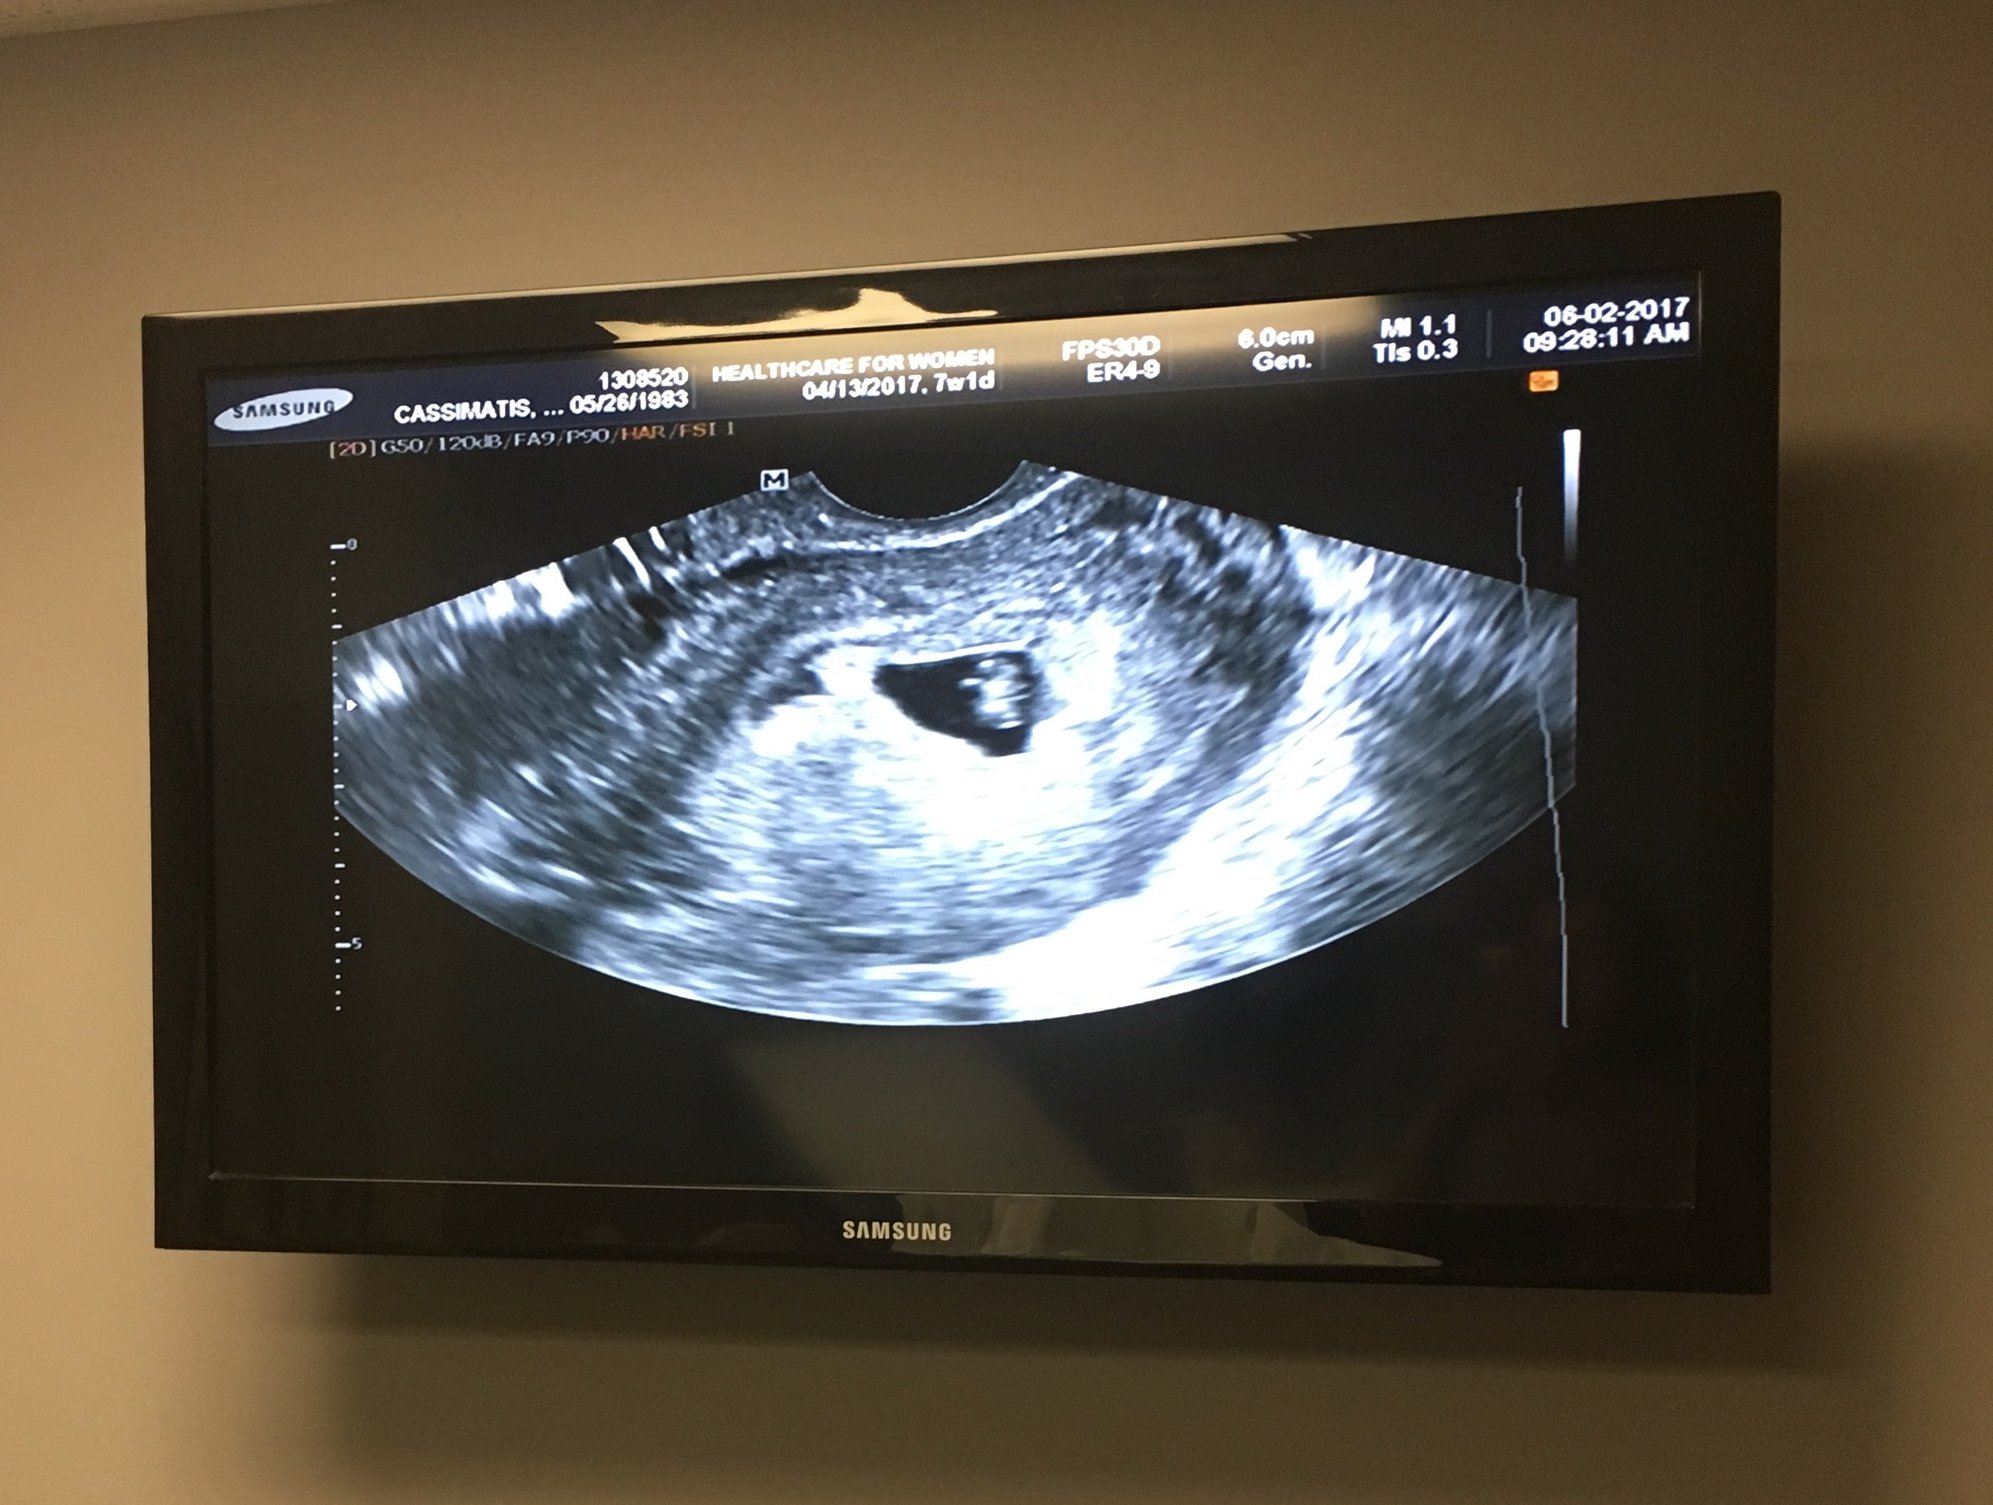

Here's our little one, measuring one day behind our due date based on LMP, but Dr. didn't see the need to adjust it and confirmed I'm 6 wks 4 days. We didn't get to hear the heartbeat, but we got to see it flutter and beat on the screen, which was so magical to me! I can't believe this is real life.